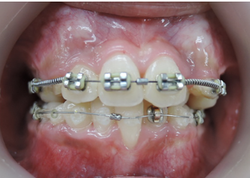

次にMEAW(マルチループ)を利用する事で咬み合わせの高さや前歯の傾斜を整えていきます。

また、MEAW(マルチループ)はゴムを24時間使用する事で最大の効果を発揮することが出来ます。

当院では簡易なMEAW(マルチループ)を使用する事で上下の前歯部をより綺麗な歯並びにしていきます。

この時にも24時間使用するゴムが大切です。

MEAW(マルチループ)により咬合高径(咬み合わせの高さ)を改善して美しい咬み合わせに治療していきます。(矯正開始から3カ月後)

この過程で歯並びが整いMEAW(マルチループ)を装着しやすくなります。

MEAW(マルチループ)を使用する事で顎偏位により左右の咬合高径(咬み合わせの高さ)の改善をしています。その治療により左右の顎のズレが改善されます。